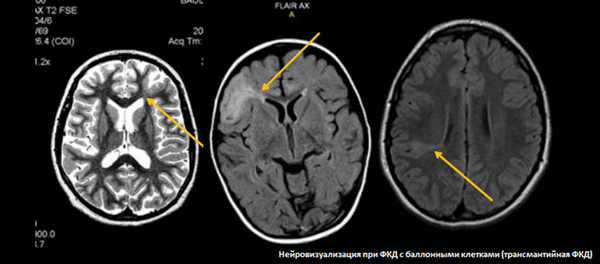

На снимках МРТ стрелками указаны участки кортикальной дисплазии - врожденного нарушения распределения клеток серого и белого веществ мозга